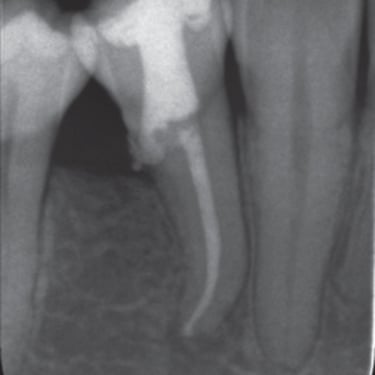

Perforación Radicular

Una perforación radicular es una abertura anormal en la raíz del diente, generalmente debido a un procedimiento dental fallido o una caries profunda.

Los pacientes pueden sentir dolor y notar hinchazón en la encía.

El tratamiento incluye la reparación de la perforación y el tratamiento de conducto. Es crucial reparar la perforación para evitar una infección.